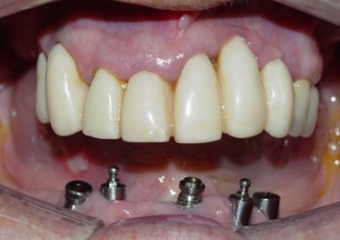

Imagens após remoção dos dentes e do implante comprometido